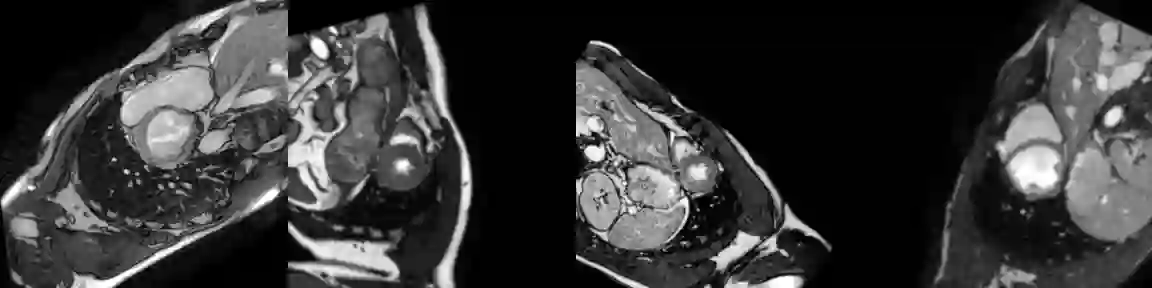

Training medical image segmentation models usually requires a large amount of labeled data. By contrast, humans can quickly learn to accurately recognise anatomy of interest from medical (e.g. MRI and CT) images with some limited guidance. Such recognition ability can easily generalise to new images from different clinical centres. This rapid and generalisable learning ability is mostly due to the compositional structure of image patterns in the human brain, which is less incorporated in medical image segmentation. In this paper, we model the compositional components (i.e. patterns) of human anatomy as learnable von-Mises-Fisher (vMF) kernels, which are robust to images collected from different domains (e.g. clinical centres). The image features can be decomposed to (or composed by) the components with the composing operations, i.e. the vMF likelihoods. The vMF likelihoods tell how likely each anatomical part is at each position of the image. Hence, the segmentation mask can be predicted based on the vMF likelihoods. Moreover, with a reconstruction module, unlabeled data can also be used to learn the vMF kernels and likelihoods by recombining them to reconstruct the input image. Extensive experiments show that the proposed vMFNet achieves improved generalisation performance on two benchmarks, especially when annotations are limited. Code is publicly available at: https://github.com/vios-s/vMFNet.